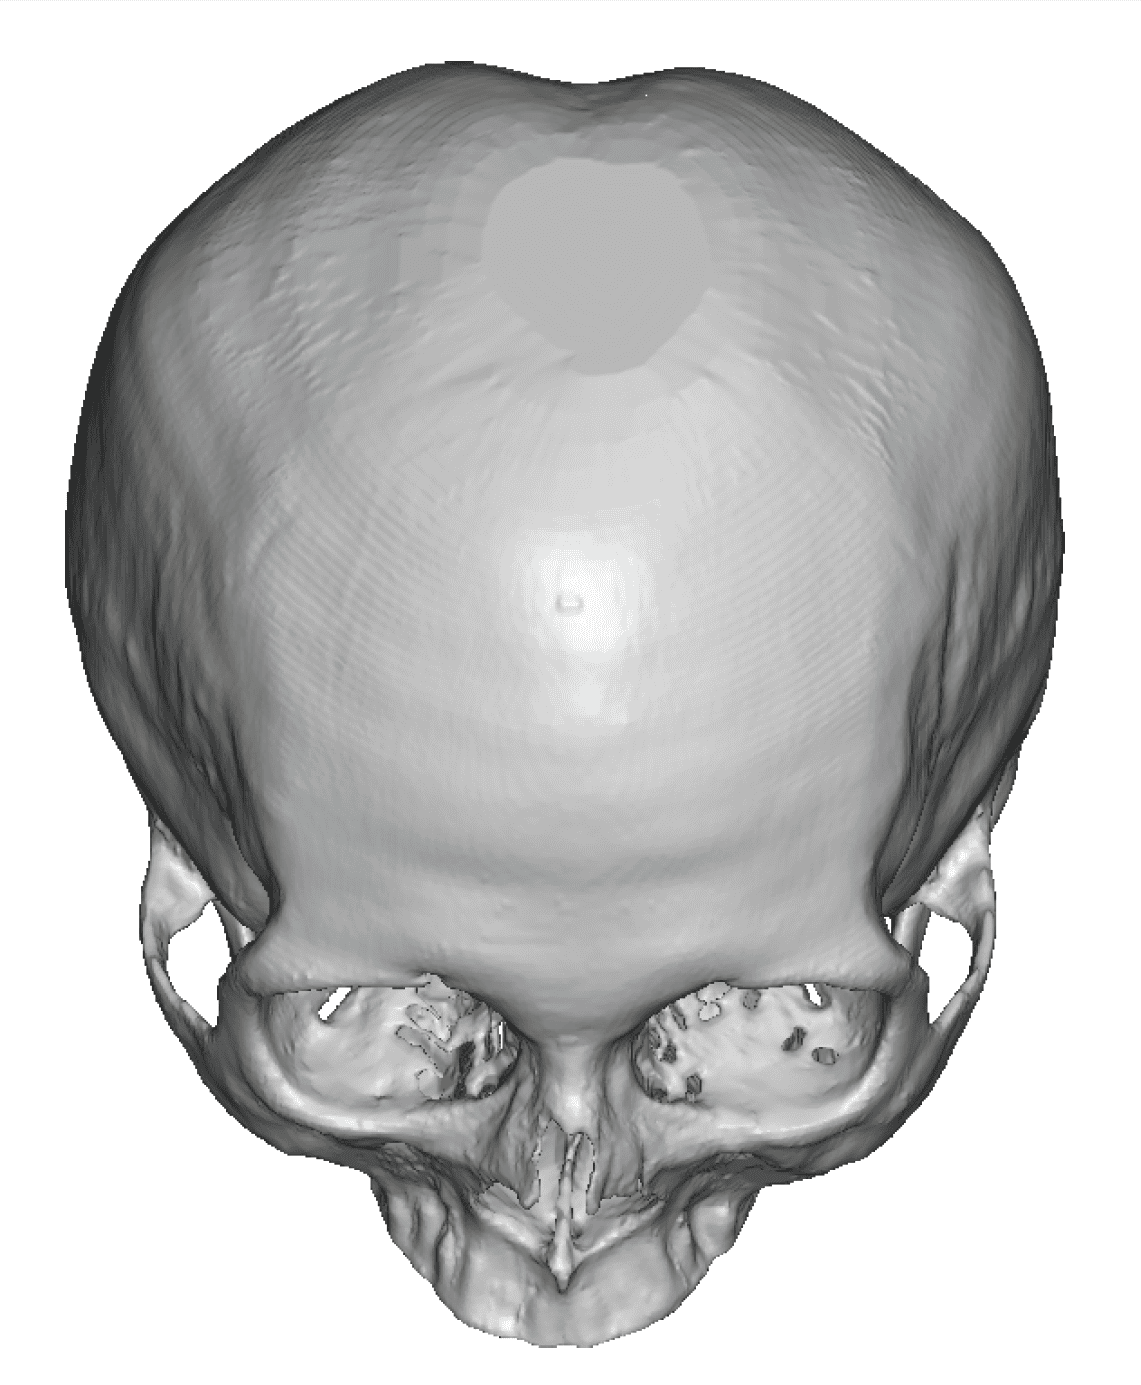

Patient 28

Desire for rounder shape to the top of the head from a congenital parasagittal deficiency skull shape.

Custom skull implant designed to fill in the parasagittal deficiencies.

Desire for rounder shape to the top of the head from a congenital parasagittal deficiency skull shape.

Custom skull implant designed to fill in the parasagittal deficiencies.